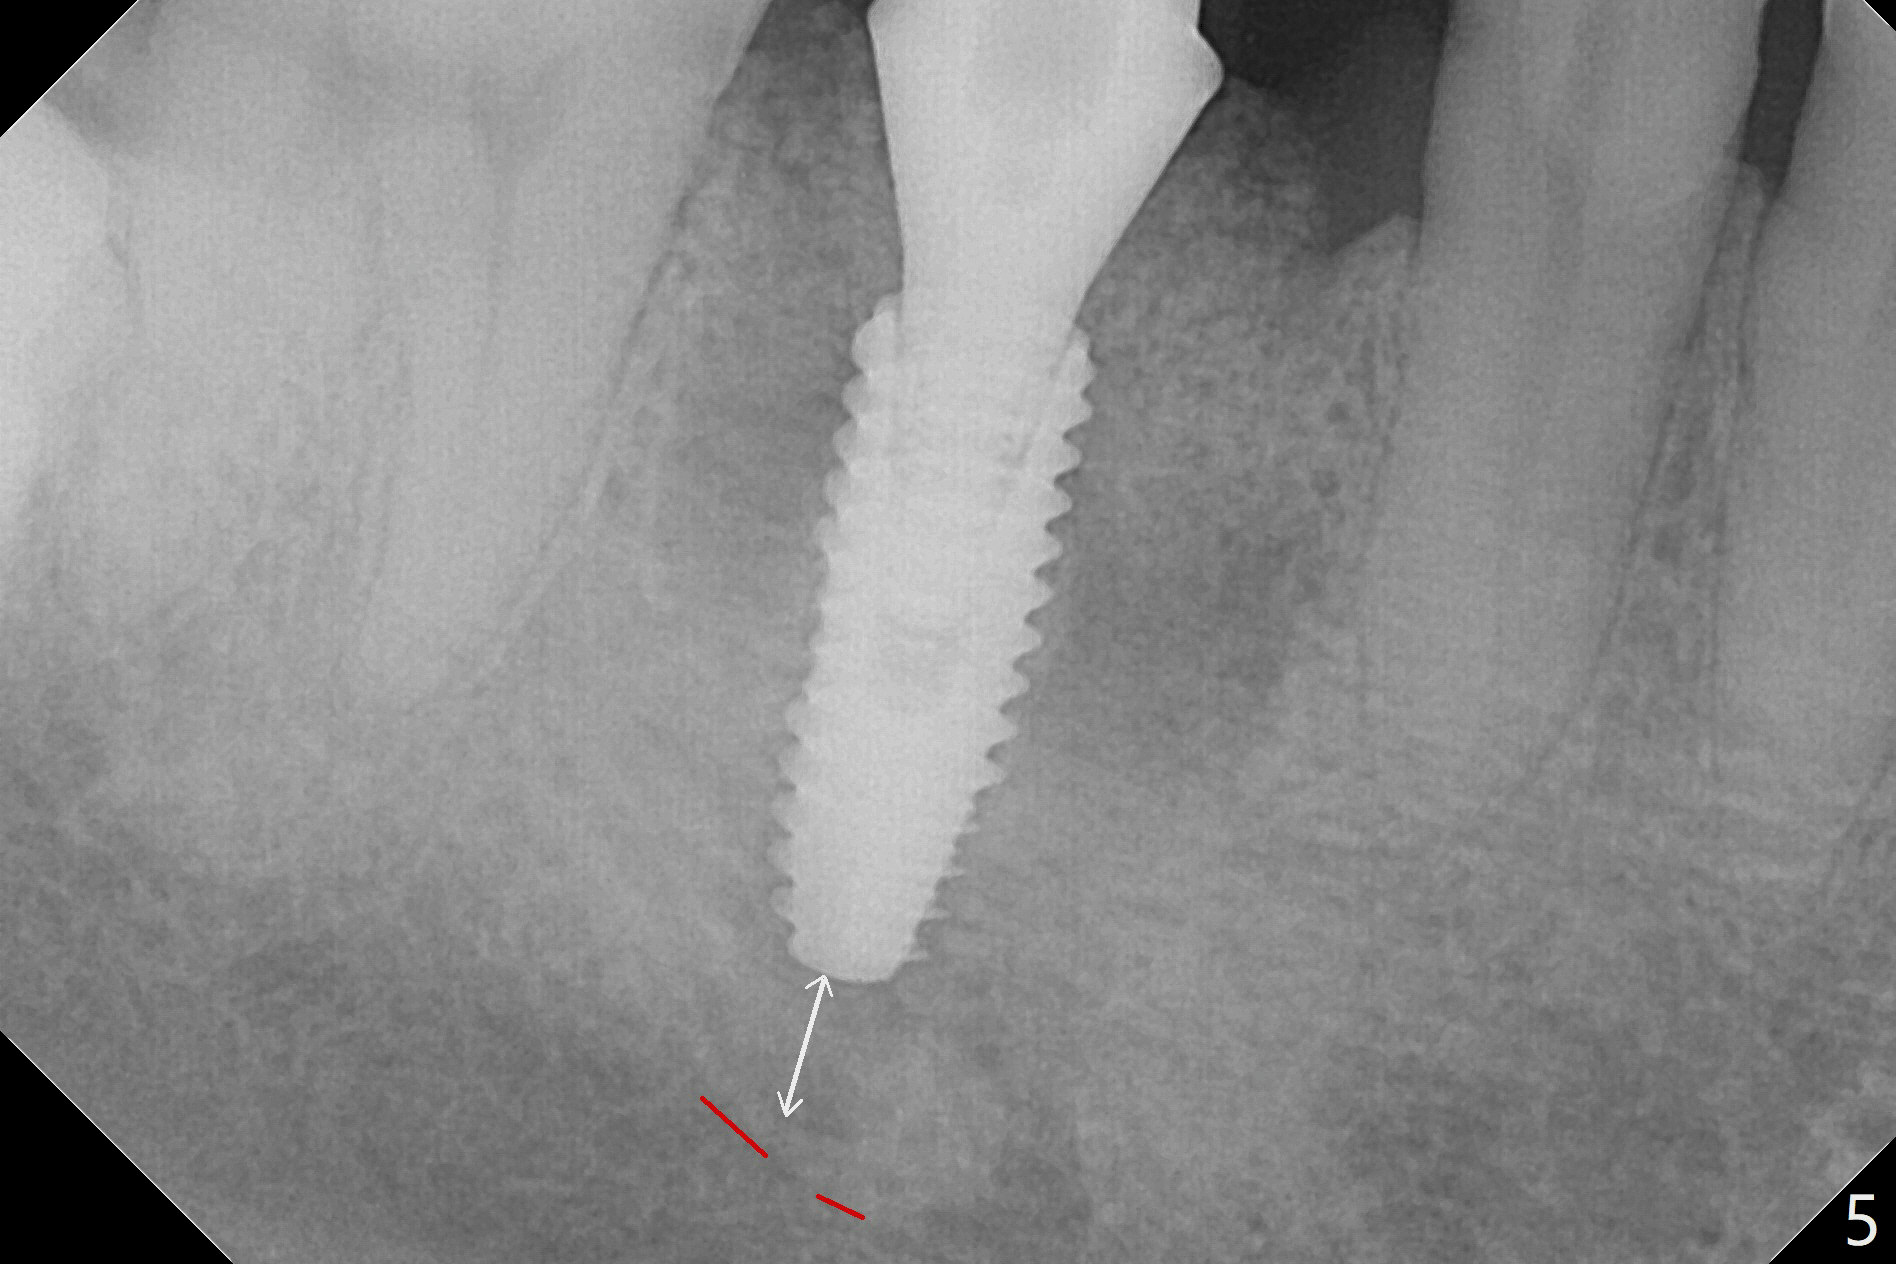

After extraction of the tooth #30, the mesiobuccal plate is found to be lost, corresponding to the fistula (Fig.1 <). Osteotomy is initiated in the flattened septum (lingual) for 13 mm (Fig.2). The patient feels pain when larger drills are being used. Marcaine has to be injected in an infiltration manner for pain control. When a 4.5x10 mm dummy implant is inserted with 55 Ncm, the end of the osteotomy (Fig.3 white line) is close to the Inferior Alveolar Canal (red dashed line). When a definitive implant (Fig.4: 4.5x11.5 mm) is placed with primary stability, there is an apical space (Fig.5 white double arrows). There is moderate postop pain. A shorter implant (10 mm) should be tried when the bone is dense. It will be associated with less pain. The fistula disappears 7 days postop (Fig.6). Although the patient appreciates that the pain is gone, there is atrophy mesiobuccally 2 months postop (Fig.7 *). The implant seems to be have been placed too buccally (Fig.8). With loss of the buccal plate, the implant should be placed away from it to prevent periimplantitis. The abutment is changed from 6.5x4(4) to 6.5x5.5 (3) mm with fabrication of a new provisional. The buccal margin is still supragingival 6 months postop and prep lower before impression. The mesial and distal sockets appear to have healed (Fig.9). When the crown is cemented, the mesiobuccal papilla is present (Fig.10 *), while the mesiolingual one is apparently absent (Fig.11 *). Using a temporary abutment and relining the provisional multiple times would increase the chance of rebuilding the missing papilla. The bone density around the implant increases 11 months post cementation (Fig.12). The dense (apparently cortical) bone seem to grow over the implant plateau 11 months post cementation (Fig.13 <).